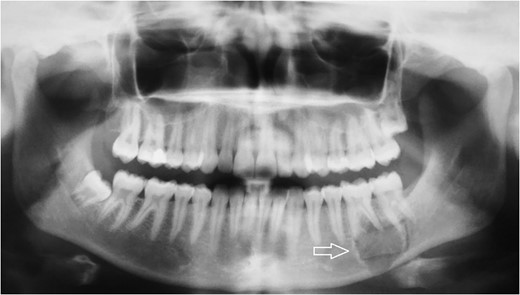

Radiologic diagnostics in two planes with panoramic X-ray. The panoramic radiograph showed a 2 × 1.8-cm radiolucent lesion of the left mandible. The lesion involved both apices of the first molar and the mesial apex of the second molar and extended to the caudal border of the mandibular bone.